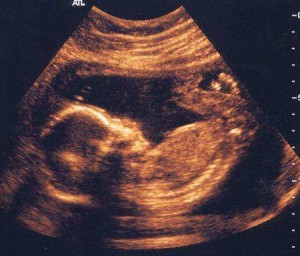

Ультразвук разбивает всю эту уклончивую риторику. Он показывают реальность будущего ребенка. Что касается заявлений аборт-провайдеров, которые называют ультразвук «жестоким» или «орудием пытки», любой, кто слушал женщин, которые сожалеют об аборте, может подтвердить их слова: «Я жалею, что не было больше информации. Если бы было известно, что собой представляет в действительности аборт и ребенок, я не была бы одна».

«Она могла двигаться. Она могла просто перемещаться, оглядываясь, сосать большой палец. … Это было настолько реалистично. Казалось, что вы можете просто дотянуться туда и забрать ребенка. Я знаю, что у них есть сердцебиение от 4 недель, но он все еще не является столь реальным для вас, пока вы не увидите этого маленького человека. Это поразило меня».

Многие сотрудники клиник меняют свое отношение к ребенку и аборту после наблюдения с помощью УЗИ. В настоящее время, многие люди в Пролайф Движении слышали историю Эбби Джонсон, директора клиники планируемого родительства, которая стала пролайфером после просмотра аборта 13-недельного нерожденного ребенка на УЗИ.

Доктор Стюарт Кэмпбелл, совершал аборты в течение многих лет, но новые, яркие, 3-D ультразвуковые изображения помогли ему переосмыслить эту практику:

«Даже когда плод лежал уже мертвый не передать ужас, который испытываешь, видя ребенка, который недавно двигал руками и ногами, открывал свой рот, сосал большой палец, … Это было жизненно важно и изменило мой взгляд. Я не думаю, что есть сомнения по этому поводу». (12)

Доктор Рэндалл, цитируемый ранее, свидетельствовал о следующем:

«Я думаю, что самое большое, что сыграло свою роль в изменении отношения это ультразвук. Ультразвук показывает в реальном времени картину жизни ребенка на экране. Ребенок действительно ожил на телемониторе и двигается. И эта картина беспокоит меня больше всего на свете».

Он заявил об этом на конференции «Знакомство с абортами», организованной Лигой действия Пролайф. Феномен работников абортивных клиник, которые после просмотра ультразвукового изображения отказались проводить аборты, был настолько распространен в течение последних нескольких десятилетий, что основные медицинские публикации обратились к этой проблеме. Согласно статье, опубликованной в OBGYN:

«Сотрудники абортариев также могут быть эмоционально затронуты ультразвуковым изображением, это может привести к изменению отношения и приоритетов». (13)